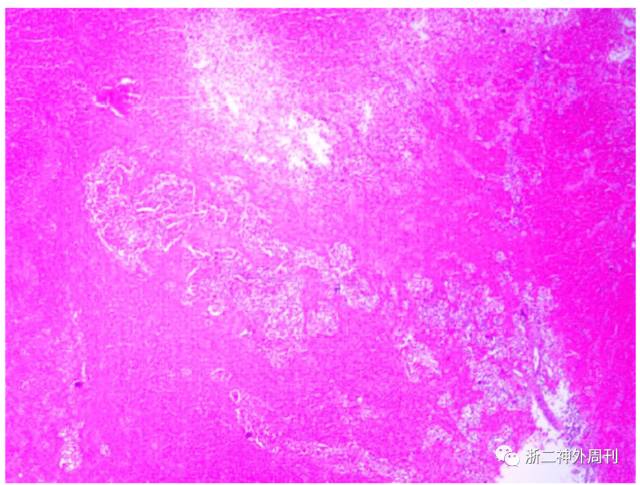

病理结果:术后我院常规病理提示:(鞍区)垂体腺瘤,伴砂砾体,出血坏死,垂体卒中。结合免疫组化结果,符合催乳素生长激素细胞腺瘤。免疫组化结果:ACTH -,Prolactin +,GH +,FSH -,LH -,ER -,PR -,TSH -,CAM5.2 核旁+,P53 个别+,Ki-67 <3%,EMA -,PR -(图6)。

图6. HE染色可见腺瘤组织(右下角有核细胞)被大片出血坏死组织(染色较深组织)包绕,考虑垂体卒中。